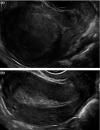

Purpose: To evaluate the reliability of the sonographic subserosal hypoechoic rim sign and endomyometrial junction indistinctness in distinguishing patients with acute puerperal endometritis from other common postpartum complications, particularly those with retained products of conception.

Results: The average sensitivity and specificity for readers identifying the subserosal hypoechoic rim sign in full-term postpartum patients with acute endometritis were 76.9% and 92.1%, respectively. Interobserver reliability was moderate with a kappa value of 0.5. The average sensitivity and specificity for endomyometrial junction indistinctness were 89.0% and 95.2%, respectively, with substantial inter-observer agreement, Kappa 0.7. These signs remained specific but were less frequently observed in postpartum patients scanned during early pregnancy.

Conclusion: We have shown that identifying the subserosal hypoechoic rim and endomyometrial junction indistinctness on ultrasound scans can reliably help to distinguish patients with acute postpartum endometritis from other complications, particularly in full-term postpartum patients.